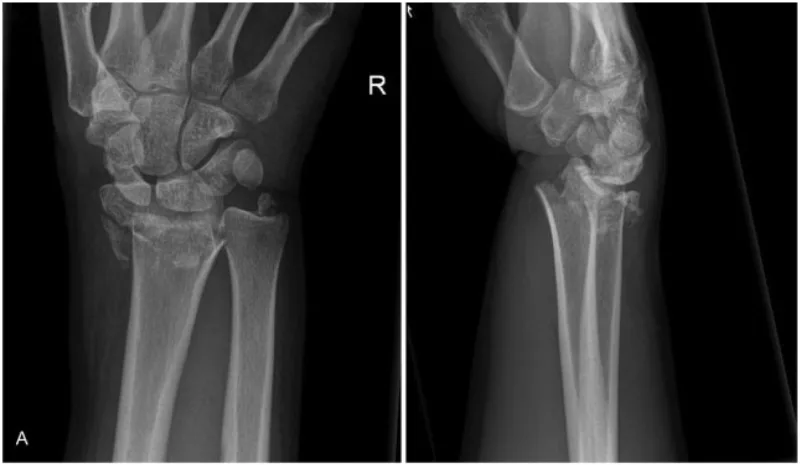

15時過ぎに救急車到着. 手関節はフォーク状変形を呈し, 橈骨遠位端骨折を強く疑いました. 足部も腫脹と変形が顕著で, 踵骨骨折の可能性大. X線とCTを迅速に撮像しました.

結果は, 手舟状骨骨折, 橈骨遠位端骨折, 尺骨茎状突起骨折, さらに踵骨骨折を合併. それぞれ透視下で整復し, ギプス副子固定を実施しました. 帰宅を希望されましたが, 歩行困難のため, 家族の説得もあり入院となりました.